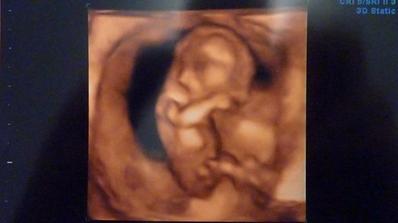

Prekvapkoo 🙂

Je to az neskutočne, ked som objavila tieto stránky, mali sme tesne pred svadbou, trávila som čas na mojasvadba.sk, po svadbe sme začali rekonštruovat, tak som sa nalepila na modrastrecha.sk. a vyše mesiaca už chodim na modrého konika až sa to asi na mna nalepilo a minulý týždeň som ostala prekvapená z //. Tak tu už nalepená asi aj ostanem 🙂))